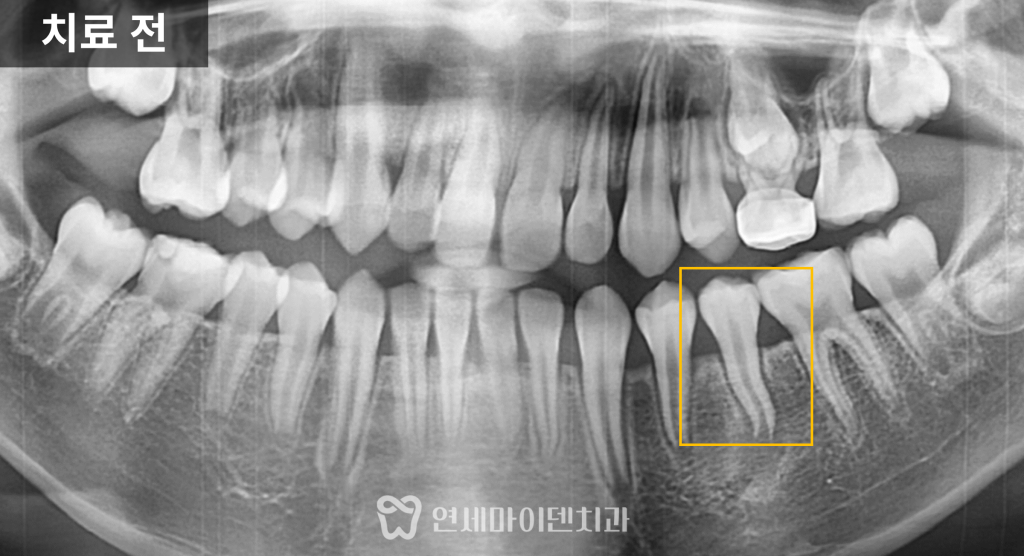

엑스레이를 확인해보니

해당 치아는 뿌리 끝이 완전히 닫히지 않은

성장 중인 상태였습니다.

하지만 충치는 보이지 않았음에도

뿌리 주변 뼈가 녹아 있는

염증 소견이 확인되었습니다.